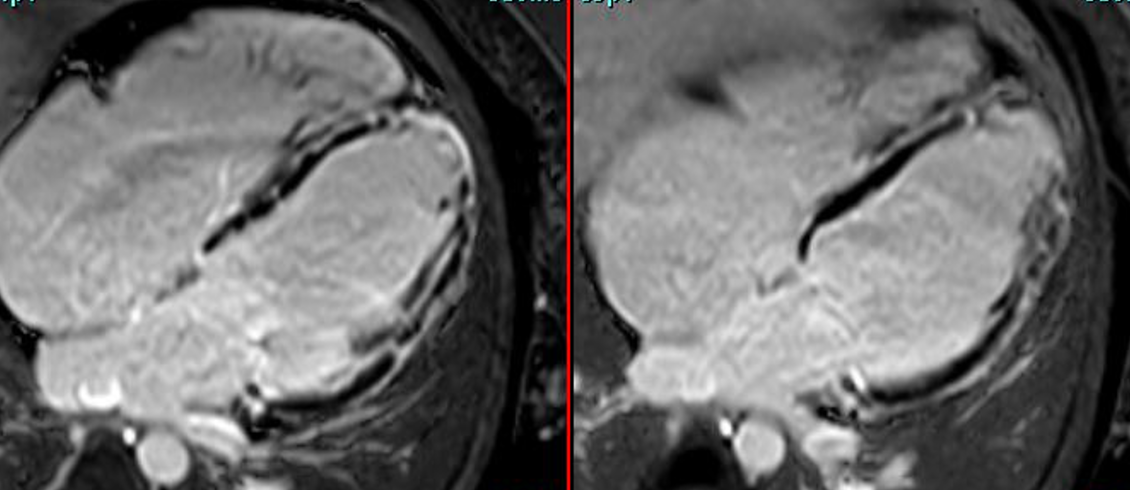

Hot phase of ACM